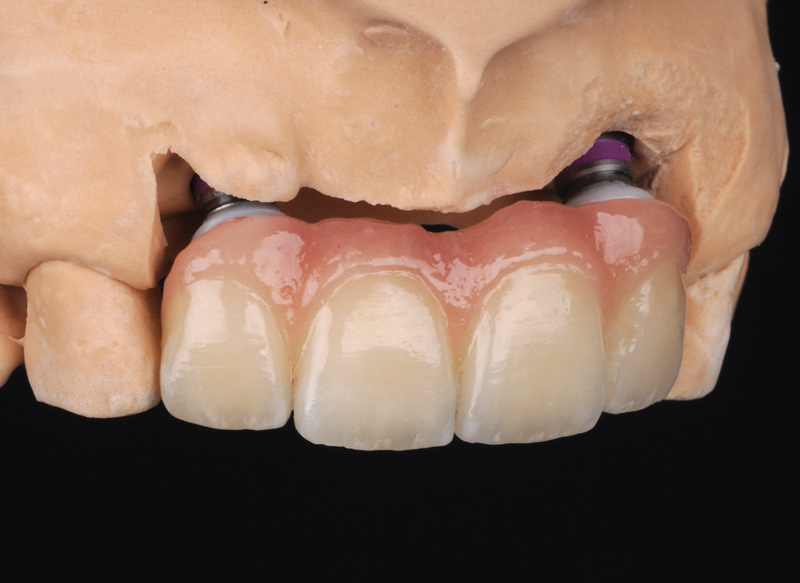

Fig 13. Porcelain-layered zirconia framework (CL-IIIb) with layered pink porcelain for the gingiva (Fig 13); final image in the mouth of the porcelain-layered zirconia framework (Fig 14) (images courtesy of Aram Torosian, MDC).

Figure 13

Fig 14. Porcelain-layered zirconia framework (CL-IIIb) with layered pink porcelain for the gingiva (Fig 13); final image in the mouth of the porcelain-layered zirconia framework (Fig 14) (images courtesy of Aram Torosian, MDC).

Figure 14